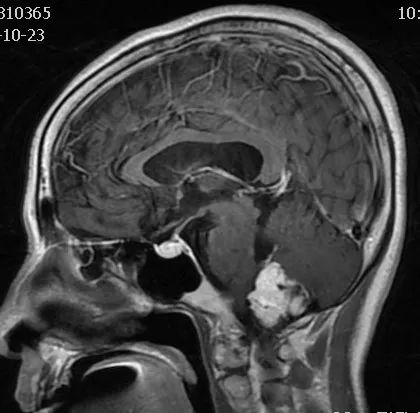

FLAIR图及T1矢状位增强:白色箭头所示小脑延髓池内可见实性占位病变,形态不规则,呈分叶状,病变边界清晰,边缘见血管流空信号影如蓝色箭头所示。

影像描述:小脑延髓池内见不规则异常信号影,呈等及稍长T1长T2信号,内部信号不均,边缘见稍粗大流空信号血管影,FLAIR病灶中心少许片状低信号,增强呈明显强化,DWI不均低信号,ADC不均高信号。小脑半球、延髓、第四脑室受压变形。临近延髓受压变窄,呈长T1长T2信号。

影像诊断:后颅窝实性占位病变,考虑实性血管母细胞瘤。